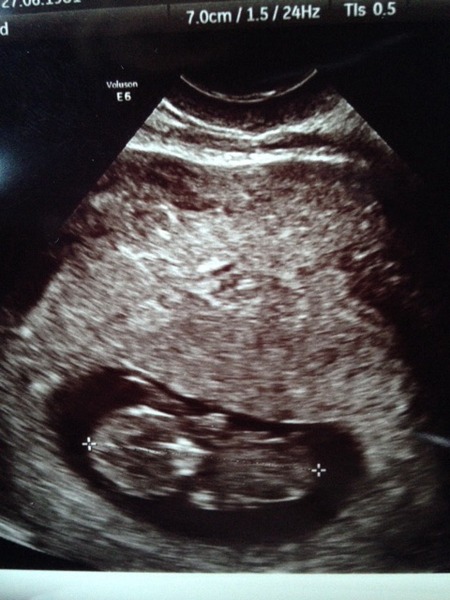

Kitty I had a scan today too - I think we are the same date-wise - 9+6?

Amazing to see little arms and legs going, DW tried to record it but unfortunately the phone didn't work dammit so will have to hope the hospital are as accommodating when we go for our 12-week scan on 17th.

Hopefully the image of the scan has worked.....

Feels so real now. Scary.

Love the scan pics Hare and Tea, very sweet little squishes! :)